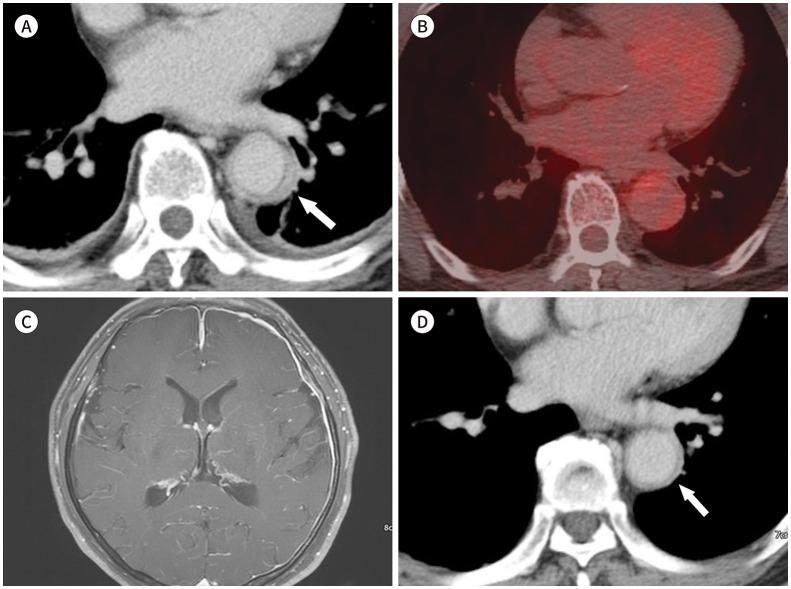

Immunoglobulin G4-related disease (IgG4-RD) is a chronic inflammatory condition involving multiple organs, including the salivary or lacrimal glands, orbit, pancreas, bile duct, liver, kidney, retroperitoneum, aorta, lung, and lymph nodes. It is histologically characterized by tissue infiltration with lymphocytes and IgG4-secreting plasma cells, storiform fibrosis, and obliterative phlebitis. In the thoracic involvement of IgG4-RD, mediastinal lymphadenopathy and perilymphangitic interstitial thickening of the lung are the most common findings. Peribronchovascular and septal thickening and paravertebral band-like soft tissue are characteristic findings of IgG4-RD. Other findings include pulmonary nodules or masses, ground-glass opacity, alveolar interstitial thickening, pleural effusion or thickening, mass in the chest wall or mediastinum, and arteritis involving the aorta and coronary artery. Radiologic differential diagnosis of various malignancies, infections, and inflammatory conditions is needed. In this review, we describe the imaging findings of IgG4-RD and the radiologic differential diagnoses in the thorax.

免疫球蛋白G4相关性疾病(IgG4-RD)是一种累及多个器官的慢性炎症性疾病,这些器官包括唾液腺或泪腺、眼眶、胰腺、胆管、肝脏、肾脏、腹膜后、主动脉、肺和淋巴结。其组织学特征为淋巴细胞和分泌IgG4的浆细胞浸润组织、席纹状纤维化和闭塞性静脉炎。在IgG4-RD累及胸部时,纵隔淋巴结肿大和肺淋巴管周围间质增厚是最常见的表现。支气管血管周围和小叶间隔增厚以及椎旁带状软组织是IgG4-RD的特征性表现。其他表现包括肺结节或肿块、磨玻璃影、肺泡间质增厚、胸腔积液或增厚、胸壁或纵隔肿块以及累及主动脉和冠状动脉的动脉炎。需要对各种恶性肿瘤、感染和炎症性疾病进行影像学鉴别诊断。在本综述中,我们描述了IgG4-RD的影像学表现以及胸部的影像学鉴别诊断。